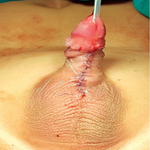

A 20-day-old female late-preterm neonate (34+4 weeks, birth weight: 920 g) born via lower segment cesarean section for breech presentation to a primigravida mother presented with a lumbosacral swelling noted at birth. The neonate cried immediately after delivery. On examination, a dorsally placed cystic swelling with exposed neural placode was observed, consistent with an open neural tube defect. Lower-limb tone was reduced, with poor spontaneous movements and absent anal reflex. No craniofacial anomalies were noted. Magnetic resonance imaging (MRI) of the spine and brain demonstrated a lumbosacral meningomyelocele with herniation of neural elements through a bony defect, along with features of Chiari II malformation, including downward displacement of cerebellar tonsils and a small posterior fossa. The three differential diagnoses included meningocele, terminal myelocystocele, and lipomyelomeningocele. These findings confirmed meningomyelocele with associated Chiari II malformation. Screening cranial ultrasound showed mild ventriculomegaly. The neonate was managed in the neonatal intensive care unit (NICU) with a sterile dressing of the lesion, prone positioning, infection prevention measures, and fluid/electrolyte monitoring. Neurosurgical repair of the defect was planned (or completed on the day after birth). Supportive physiotherapy included positioning, maintaining skin integrity, and monitoring lower-limb responses. Postoperatively, the neonate remained hemodynamically stable with no immediate surgical complications. Neurological status and head circumference are being monitored for potential development of hydrocephalus.

Figure 1: Chiari II-associated meningomyelocele